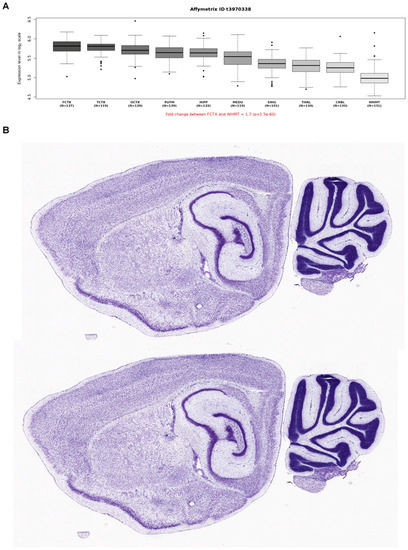

2.3. Expression and Protein-Protein Interaction Analyses

To better understand the central neurological anomalies and the neurodevelopmental (regressive) features observed in our NHS family, we also explored the mRNA brain expression data as well as potential interactors of NHS using publicly availably web-based tools and datasets. To this end, we first interrogated microarray data (Affymetrix Exon 1.0 ST) from human post-mortem brain tissue collected by the UK Human Brain Expression Consortium as previously described [28]. This analysis showed higher expression in the frontal and temporal regions (Figure 3A); the mouse brain expression from the Allen Brain Atlas revealed high NHS expression in the frontal regions and the corpus callosum, consistent with the imaging phenotype of our family (Figure 3B). Then, we explored potential interactors of NHS using the STRING database (https://string-db.org (accessed on 19 July 2021)), and this revealed a close association with CDKL5 (Figure 4). This protein is encoded by the CDKL5 gene (MIM #300203), known to be implicated in neurodevelopmental disorders with possible regressive features.

Figure 3. Summary of NHS gene expression in human (A) and mouse (B) brain.

Figure 3A Boxplots of NHS mRNA expression levels in ten adult brain regions (source: BRAINEAC, see: http://braineac.org (accessed on 19 July 2021)). The expression levels are based on exon array experiments and are plotted on a log2 scale (y axis). This dataset was generated with Affymetrix Exon 1.0 ST arrays and brain tissue originating from 134 control individuals, collected by the Medical Research Council Sudden Death Brain and Tissue Bank. This plot shows variation in NHS expression across the ten brain regions analyzed, such that expression is higher in the frontal and temporal cortex thank in other brain regions. Abbreviations are as follows: PUTM, putamen; FCTX, frontal cortex; TCTX, temporal cortex; OCTX, occipital cortex; HIPP, hippocampus; SNIG, sub-stantia nigra; MEDU, medulla (specifically the inferior olivary nucleus); WHMT, intralobular white matter; THAL, thalamus; and CRBL, cerebellar cortex. Figure 3B NHS mRNA expression in the mouse brain in sagittal section. NHS was highly expressed in the frontal cortex and the cerebellum. Images were obtained from the Allen Mouse Brain Atlas (Allen Institute for Brain Science, see: http://mouse.brain-map.org/gene/show/83372 (accessed on 19 July 2021)). Expression intensity is color-coded in Nissl staining.